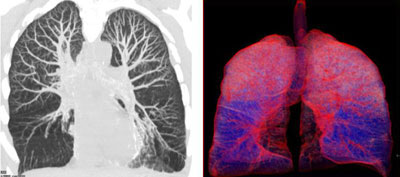

MIP (maximum intensity projection image) and color enhanced volume rendered image of a 25 year old woman with panacinar emphysema. Note the paucity of vascularity in the lower lobes on the MIP images. The blue areas in the lower lobes are the emphysematous areas while the pink areas are the normal lung.